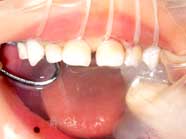

このお子さんはまだ2歳前です。

いつも哺乳瓶でミルクを飲みながら

眠りについていました。

歯の裏側にも

大きな穴が開いています

小児歯科の専門医なら

悪くなったところを取って

レジンで元のように出来ますが

哺乳瓶を続ければまた周りから

虫歯が出来てしまいます